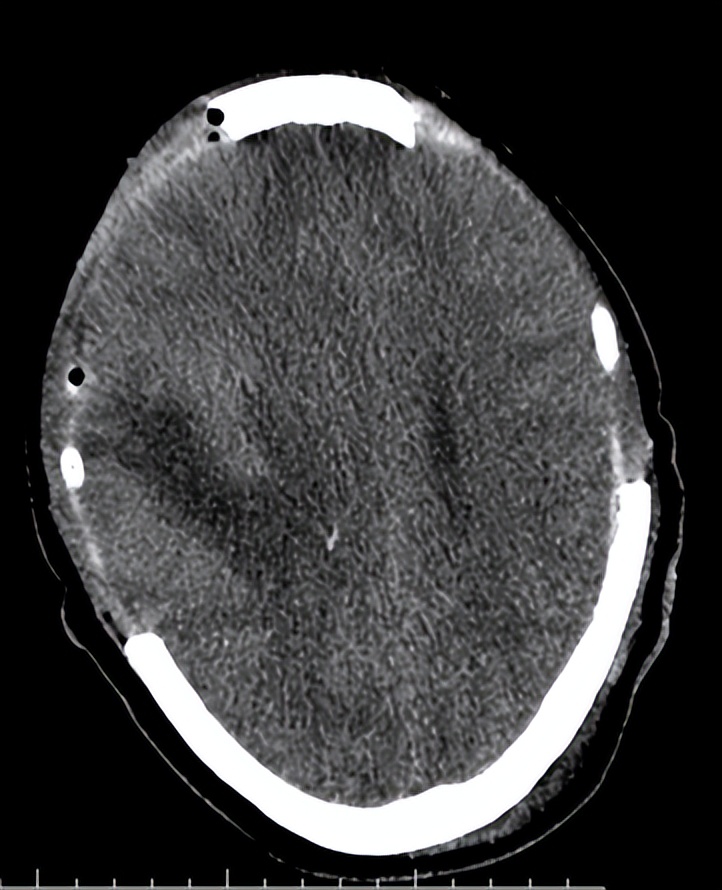

06-07日入院时头CT